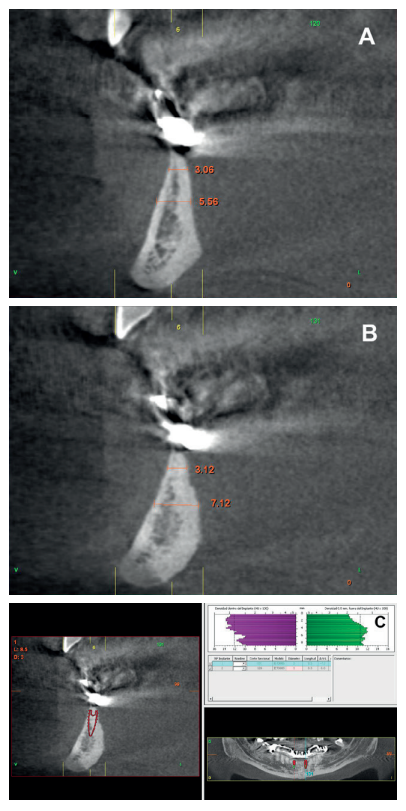

horizontal resorption of the antero-inferior sector in the incisor

area; (A) area corresponding to tooth 42 (B) area corresponding

to tooth 32 (C) Planning of the expander implant in the CT cut.